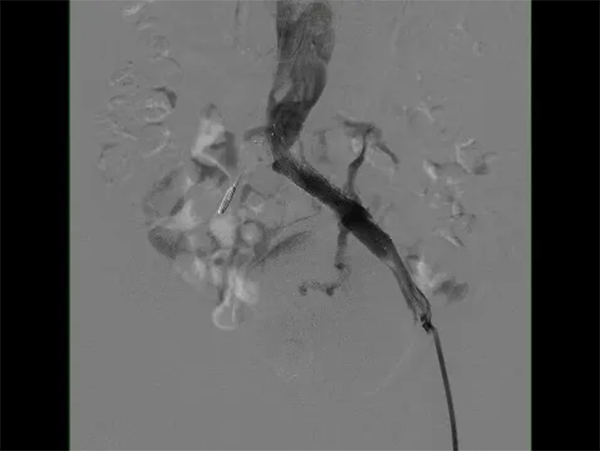

在與患者及家屬進行了詳細的交流后,患者決定住院治療。在經(jīng)過了詳細的病情分析后,介入科肖晉昌團隊為其制定了“髂靜脈造影+球囊擴張+支架置入”的治療計劃。術(shù)中造影發(fā)現(xiàn)患者左髂總靜脈近心端重度狹窄,周圍側(cè)支開放,狹窄兩端壓差明顯,均提示患者存在重度的髂靜脈壓迫(圖3)。予以球囊擴張狹窄處(圖4),然后行支架置入(圖5)。支架置入后造影患者左髂靜脈血液回流明顯改善,周圍側(cè)支減少。術(shù)后由張科醫(yī)師負責對其隨訪,經(jīng)過1個月的隨訪,患者目前下肢潰瘍基本愈合(圖6)。

圖5 支架置入